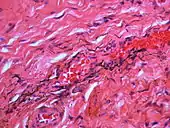

Over time, the amalgam particles embedded in the soft tissues corrode.[5]: 183 Macrophages take up the exogenous particles, and the silver in amalgam leads to staining of collagen fibers.[5]: 183

If necessary, the diagnosis can be confirmed histologically by excisional biopsy, which excludes nevi and melanomas.[3]: 138 If a biopsy is taken, the histopathologic appearance is:[1]

- Pigmented fragments of metal within connective tissue

- Staining of reticulin fibers with silver salts

- A scattered arrangement of large, dark, solid fragments or a fine, black or dark brown granules

- Large particles may be surrounded by chronically inflamed fibrous tissue

- Smaller particles surrounded by more significant inflammation, which may be granulomatous or a mixture of lymphocytes and plasma cells